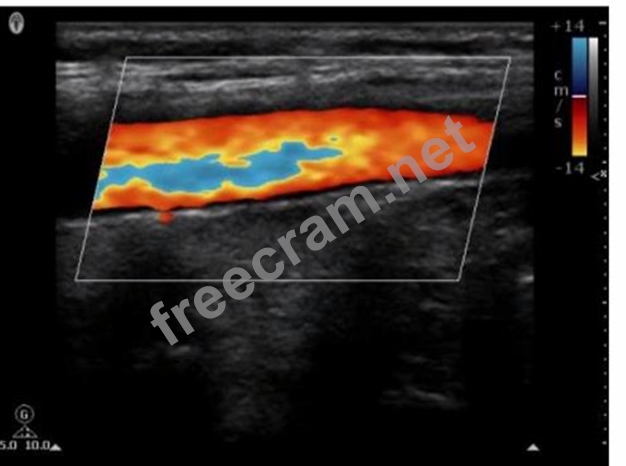

Which pulsed-wave Doppler adjustment would be appropriate to correct the aliasing seen in this image?